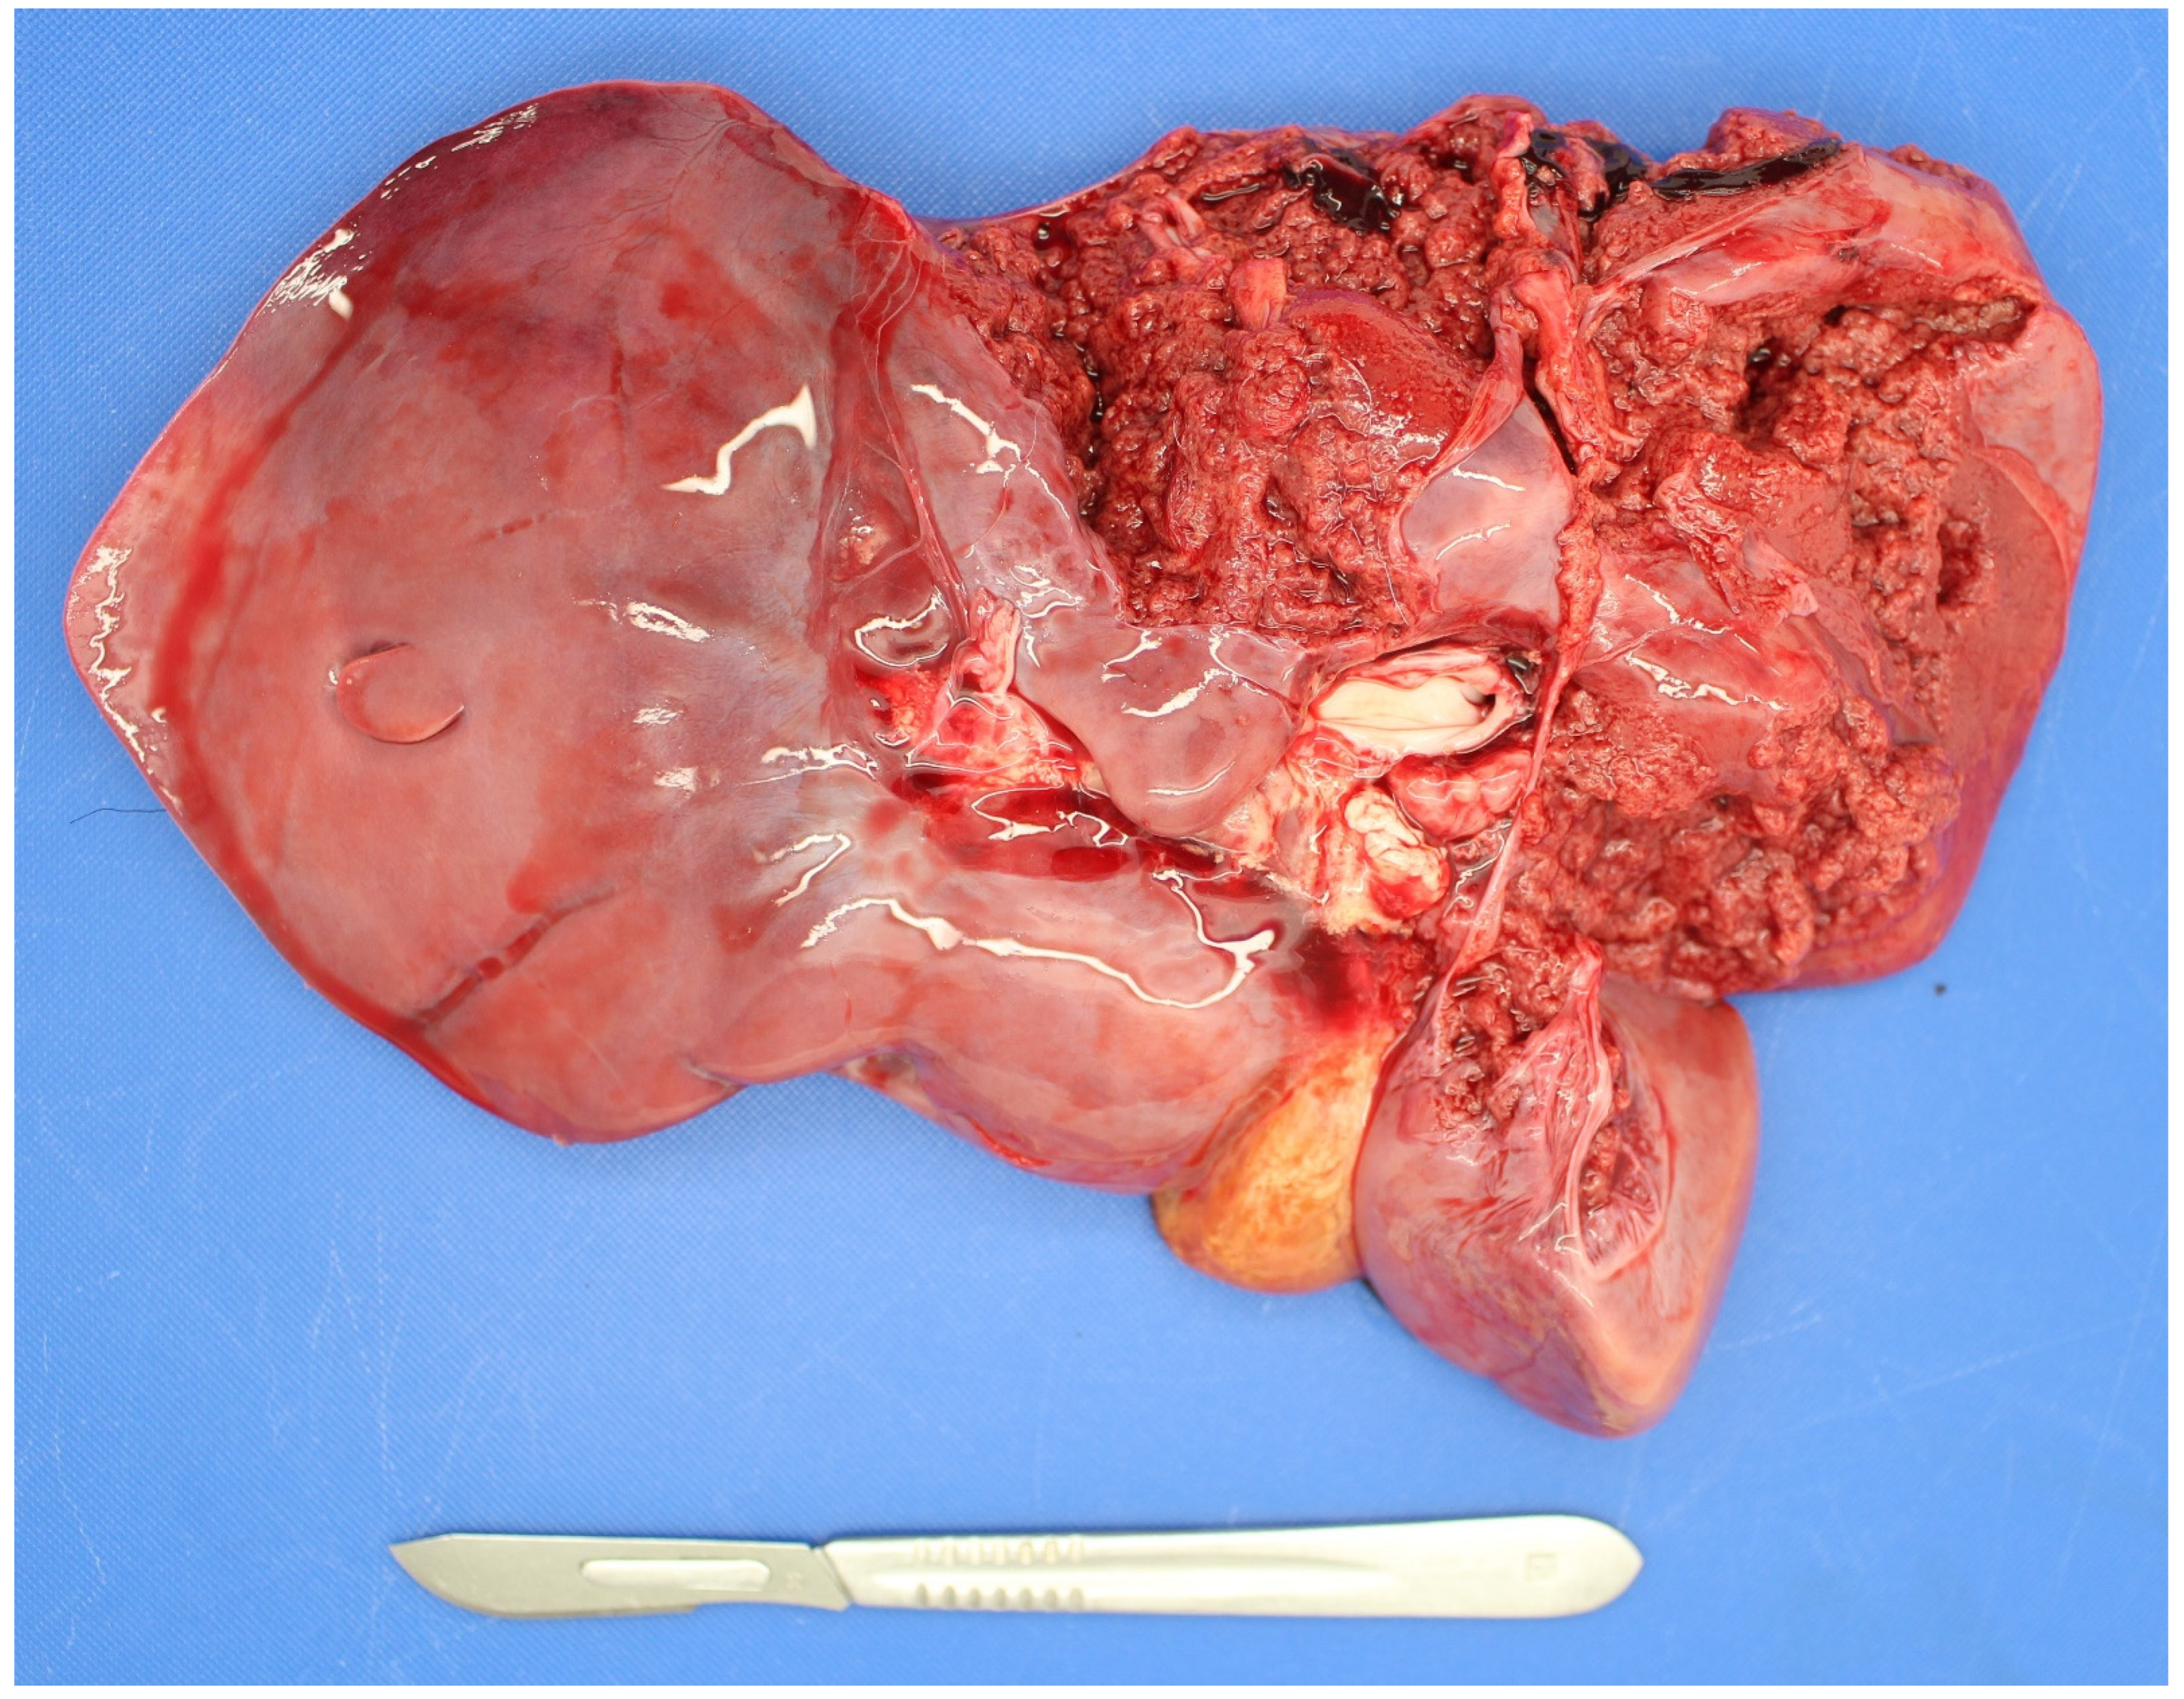

3.4. Examination of the Foetus

3.4.1. Sampling the Carcass

Microbiology Samples

3.5. Examination of the Placenta